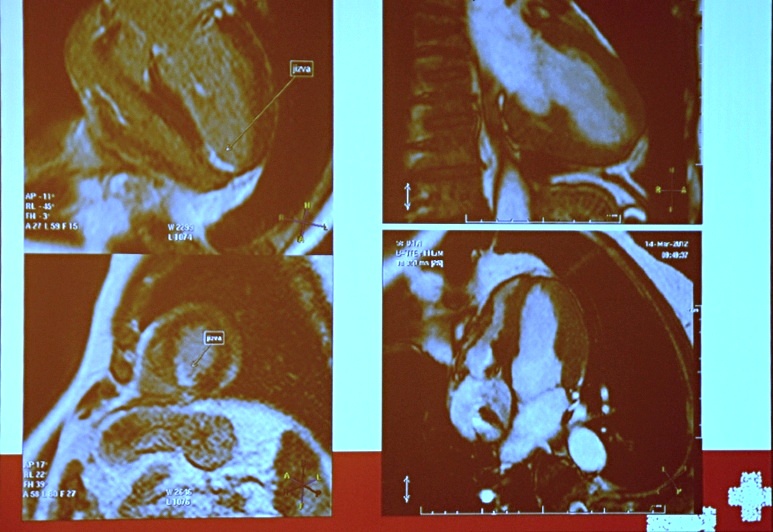

Fotogalerie - V Jablonci provedli unikátní vyšetření srdce

Otevřít související aktualitu: V Jablonci provedli unikátní vyšetření srdce